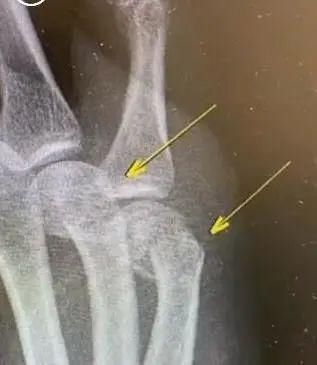

近日

上海新华医院骨科

接诊了一名男性患者

该患者到医院时

右手第四第五掌骨肿胀明显

据了解

这位爸爸是从事计算机行业的

手上伤势已经影响到工作了

最后只能住院做手术

在手掌里打了钢板

医生告诉采访人员:

“其实打娃升级到自己受伤的也有很多,但是具体升级到骨折还需要住院手术拍照的,并不多见。”